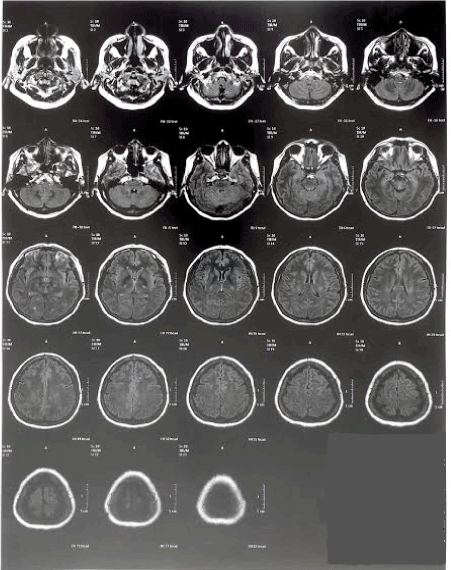

Examination of EEG indicated epileptiform activity in outbreaks in temporal areas of the right hemisphere. Her physician denied clinical significance for imaging tests a performed a susceptibility weighted imaging (SWI) (Figure 2).

Figure 2. Susceptibility weighted imaging showing basal ganglia calcification

In a new neurological evaluation, the neurosurgeon indicated that the MRI results for T1 and T2 really did not indicate clinical significance. However, SWI showed calcification of the basal ganglia, and in Flair a slight microangiopathy was observed in the frontal horn.